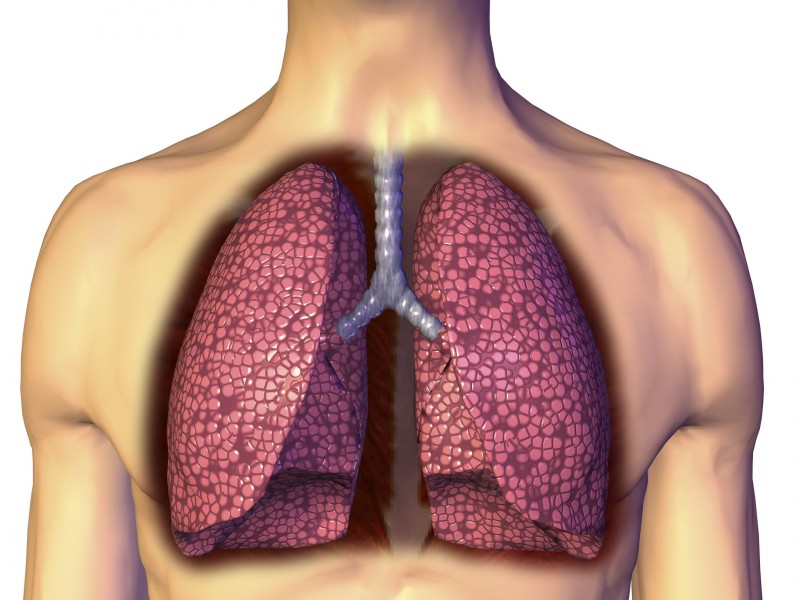

曾经有不少人认为,人体各个器官在进入老年的时候才开始衰老。然而,英国研究人员最近却表示,人体各器官的衰老时间比预想中要早得多,在我们步入老年之前,大部分器官早已开始衰老,尤其令人震惊的是,在所有的重要器官中,最先衰老的竟然是大脑和肺;而比较晚衰老的是肝脏,它在人们70岁时才开始进入衰老期。